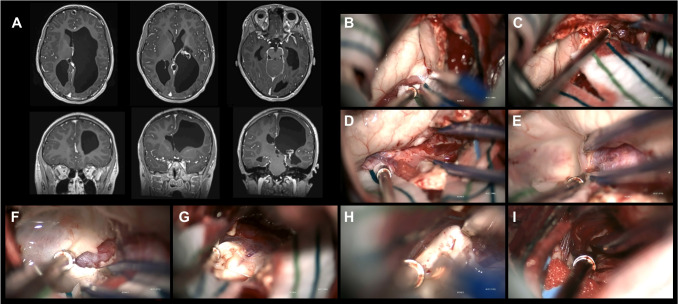

Purpose: Hemispherotomy is an effective treatment for well-selected patients with drug-resistant hemispheric epilepsy. Successful hemispherotomy leading to seizure cessation has been associated with improved neurodevelopmental outcomes and reduced healthcare utilization. This study reports seizure outcomes and complications in a large, consecutive, single-surgeon series of pediatric hemispherotomy cases using a surgical approach with modifications to previously-reported techniques.

Methods: All patients undergoing transsylvian peri-insular hemispherotomy for drug-resistant hemispheric epilepsy between May 2017 and April 2021 by a single surgeon were prospectively enrolled in an epilepsy surgery registry. With retrospective review of medical records, data were collected on baseline characteristics (demographics, epilepsy history, anti-seizure medications, neurodevelopmental status, EEG features, and imaging characteristics), operative complications, hospital course, and seizure outcomes (Engel scale at 12- and 24-month follow-up).

Results: All 32 consecutive patients (aged 15 months-19 years) were seizure-free (Engel Class 1) 12 and 24 months after hemispherotomy. At 12 months, 31 patients (97%) had Engel Class 1A outcomes, and 1 patient (3%) had an Engel Class 1D outcome. These results were maintained through 24-month follow-up. Among 31 patients taking anti-seizure medications before surgery, 22 (71%) were weaned off all agents by 24 months. One patient (3%) developed post-operative hydrocephalus requiring ventriculoperitoneal shunt placement.

Conclusion: In an etiologically heterogeneous cohort of patients undergoing hemispherotomy for drug-resistant epilepsy, a modified transsylvian peri-insular technique led to high rates of sustained seizure freedom with minimal complications.